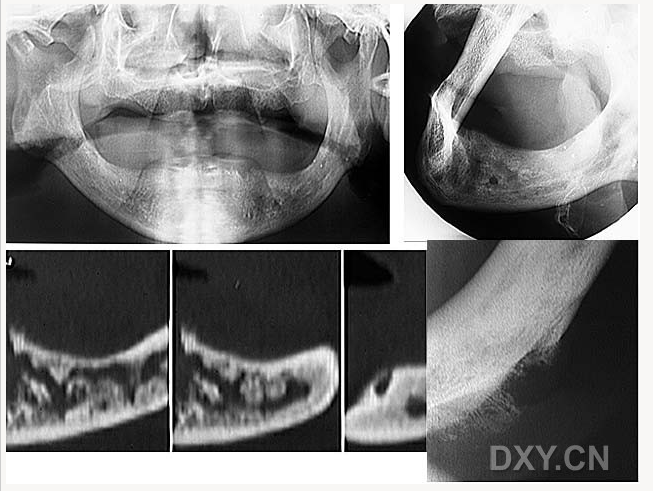

頜骨骨折